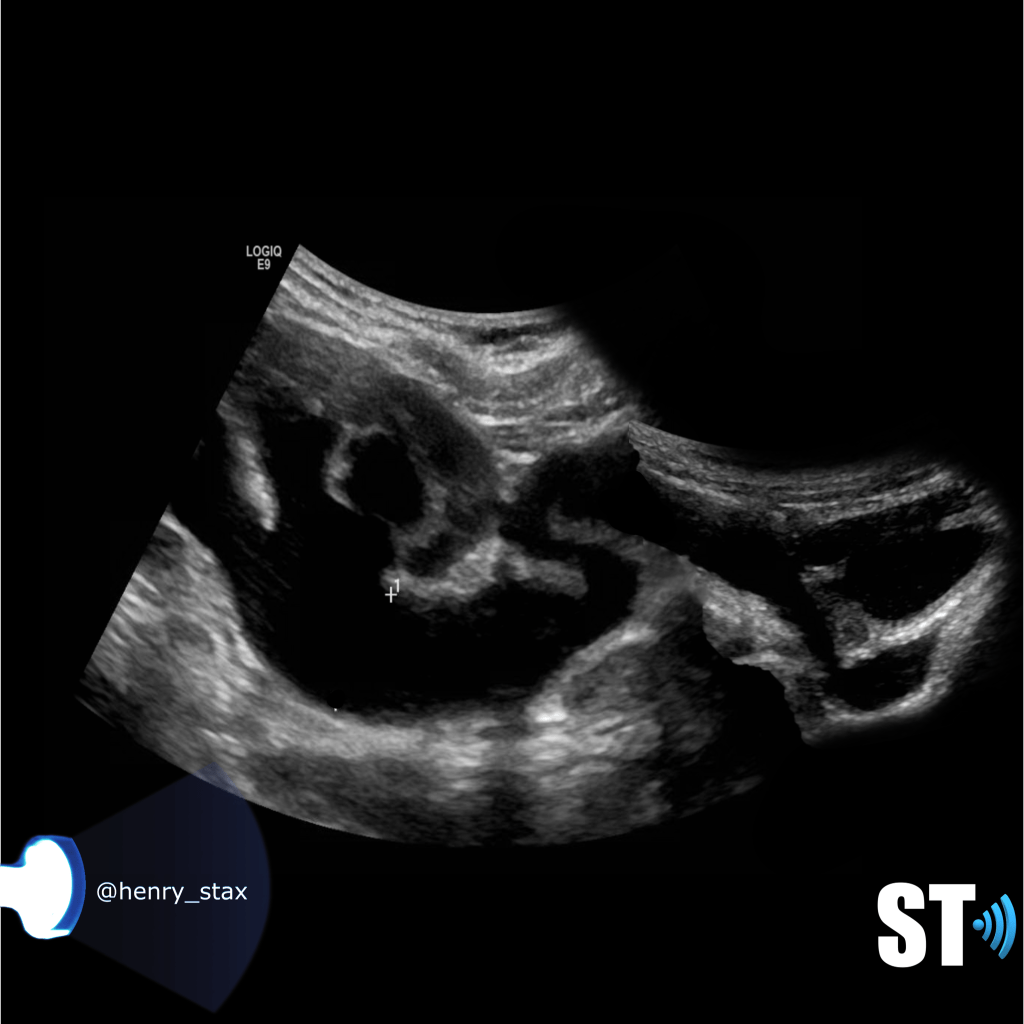

Hydronephrosis

Now for starters hydronephrosis is not a disease, it is a plumbing issue due to some underlying disease. Whether it be a tumor in the abdomen pressing on the bladder, a sneaky stone stuck in either end of the ureter, or the middle for that matter. Or some developmental anomaly causing kinked or blocked ureters.

Our job is to detect the blockage we call hydronephrosis, we may even be helpful in offering a possible cause.

A simple way to grade hydronephrosis is by severity, mild to severe.

Mild

Pelvic fullness with no calyceal dilatation

Moderate

Greater expansion of the renal pelvis and involvement of the calyces

Severe

Further dilatation of the renal collecting system with cortical thinning